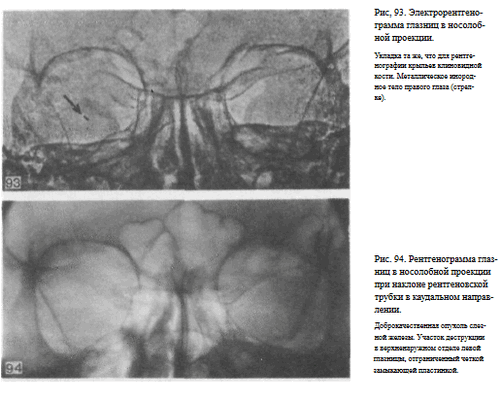

Назначение снимка — изучение контуров костей, образующих вход в глазницу, структуры верхней и наружной ее стенок, ширины и контуров верхних глазничных щелей, а также выявление инородных тел в полости глазницы.

Укладка больного для выполнения снимка, информативность снимка, критерии правильности технических условий съемки и правильности укладки те же, что для снимка крыльев клиновидной кости и верхних глазничных щелей.

В качестве примера информативности снимка глазниц в носолобной проекции для выявления инородных тел глаза и деструктивных изменений стенок приводим два наблюдения.

Одно из них — случай ранения глаза металлической стружкой (рис. 93), другое — случай деструкции верхненаружного края глазницы при доброкачественной опухоли слезной железы (рис. 94).